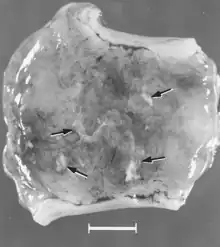

Macroscopic changes of embryos are death followed by resorption of fluids (Fig. 4) and then soft tissues (Fig. 5). Virus and viral antigen are widely distributed in tissues of infected embryos and their placentas,[84] and it is probable that microscopic lesions of necrosis and vascular damage, subsequently described for fetuses, also develop in advanced embryos.

There are numerous macroscopic changes in fetuses infected before they become immunocompetent (Fig. 6). These include a variable degree of stunting and sometimes an obvious loss of condition before other external changes are apparent; occasionally, an increased prominence of blood vessels over the surface of the fetus due to congestion and leakage of blood into contiguous tissues; congestion, edema, and hemorrhage with accumulation of serosanguineous fluids in body cavities; hemorrhagic discoloration becoming progressively darker after death; and dehydration (mummification). Many of these changes also apply to the placenta. Microscopic lesions consist primarily of extensive cellular necrosis in a wide variety of tissues and organs[95][98] (Fig. 7A). Inflammation[98] and intranuclear inclusions[95] also have been described.